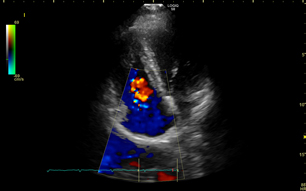

Von Mäusen und Menschen

Herzmuskelgewebe beim erwachsenen Menschen (und anderen erwachsenen Säugetieren) kann sich nach einer Schädigung durch einen Herzinfarkt nicht selbst regenerieren. Im Mutterleib entwickeln sich menschliche Babys und deren Herzen unter einem sehr geringen Sauerstoffdruck, vergleichbar mit dem in über 7000 Metern Höhe, und das Herzmuskelgewebe kann sich bis etwa eine Woche nach der Geburt regenerieren. Forscher an der Universität von Texas führten an herzinfarktgeschädigten Mäusen eine geeignete Akklimatisation durch und exponierten diese Mäuse danach für zwei Wochen einer Umgebung mit 7 Prozent Sauerstoff. Das Herzgewebe der Mäuse zeigte eine signifikante Regeneration, und es konnte nachgewiesen werden, dass sich die Herzmuskelzellen begannen zu teilen. (Nature: Hypoxia induces heart regeneration in adult mice, 2017). In der "MyoCardioGen"-Studie des DLR soll nun mit Nancy und mir als Probanden gezeigt werden, ob die sauerstoffarme Umgebung von 7000 Metern die Herzfunktion verbessert und sich erste Hinweise daraufhin finden lassen, dass sich auch die erwachsenen menschlichen Herzmuskelzellen durch Sauerstoffmangel zur Teilung anregen lassen.